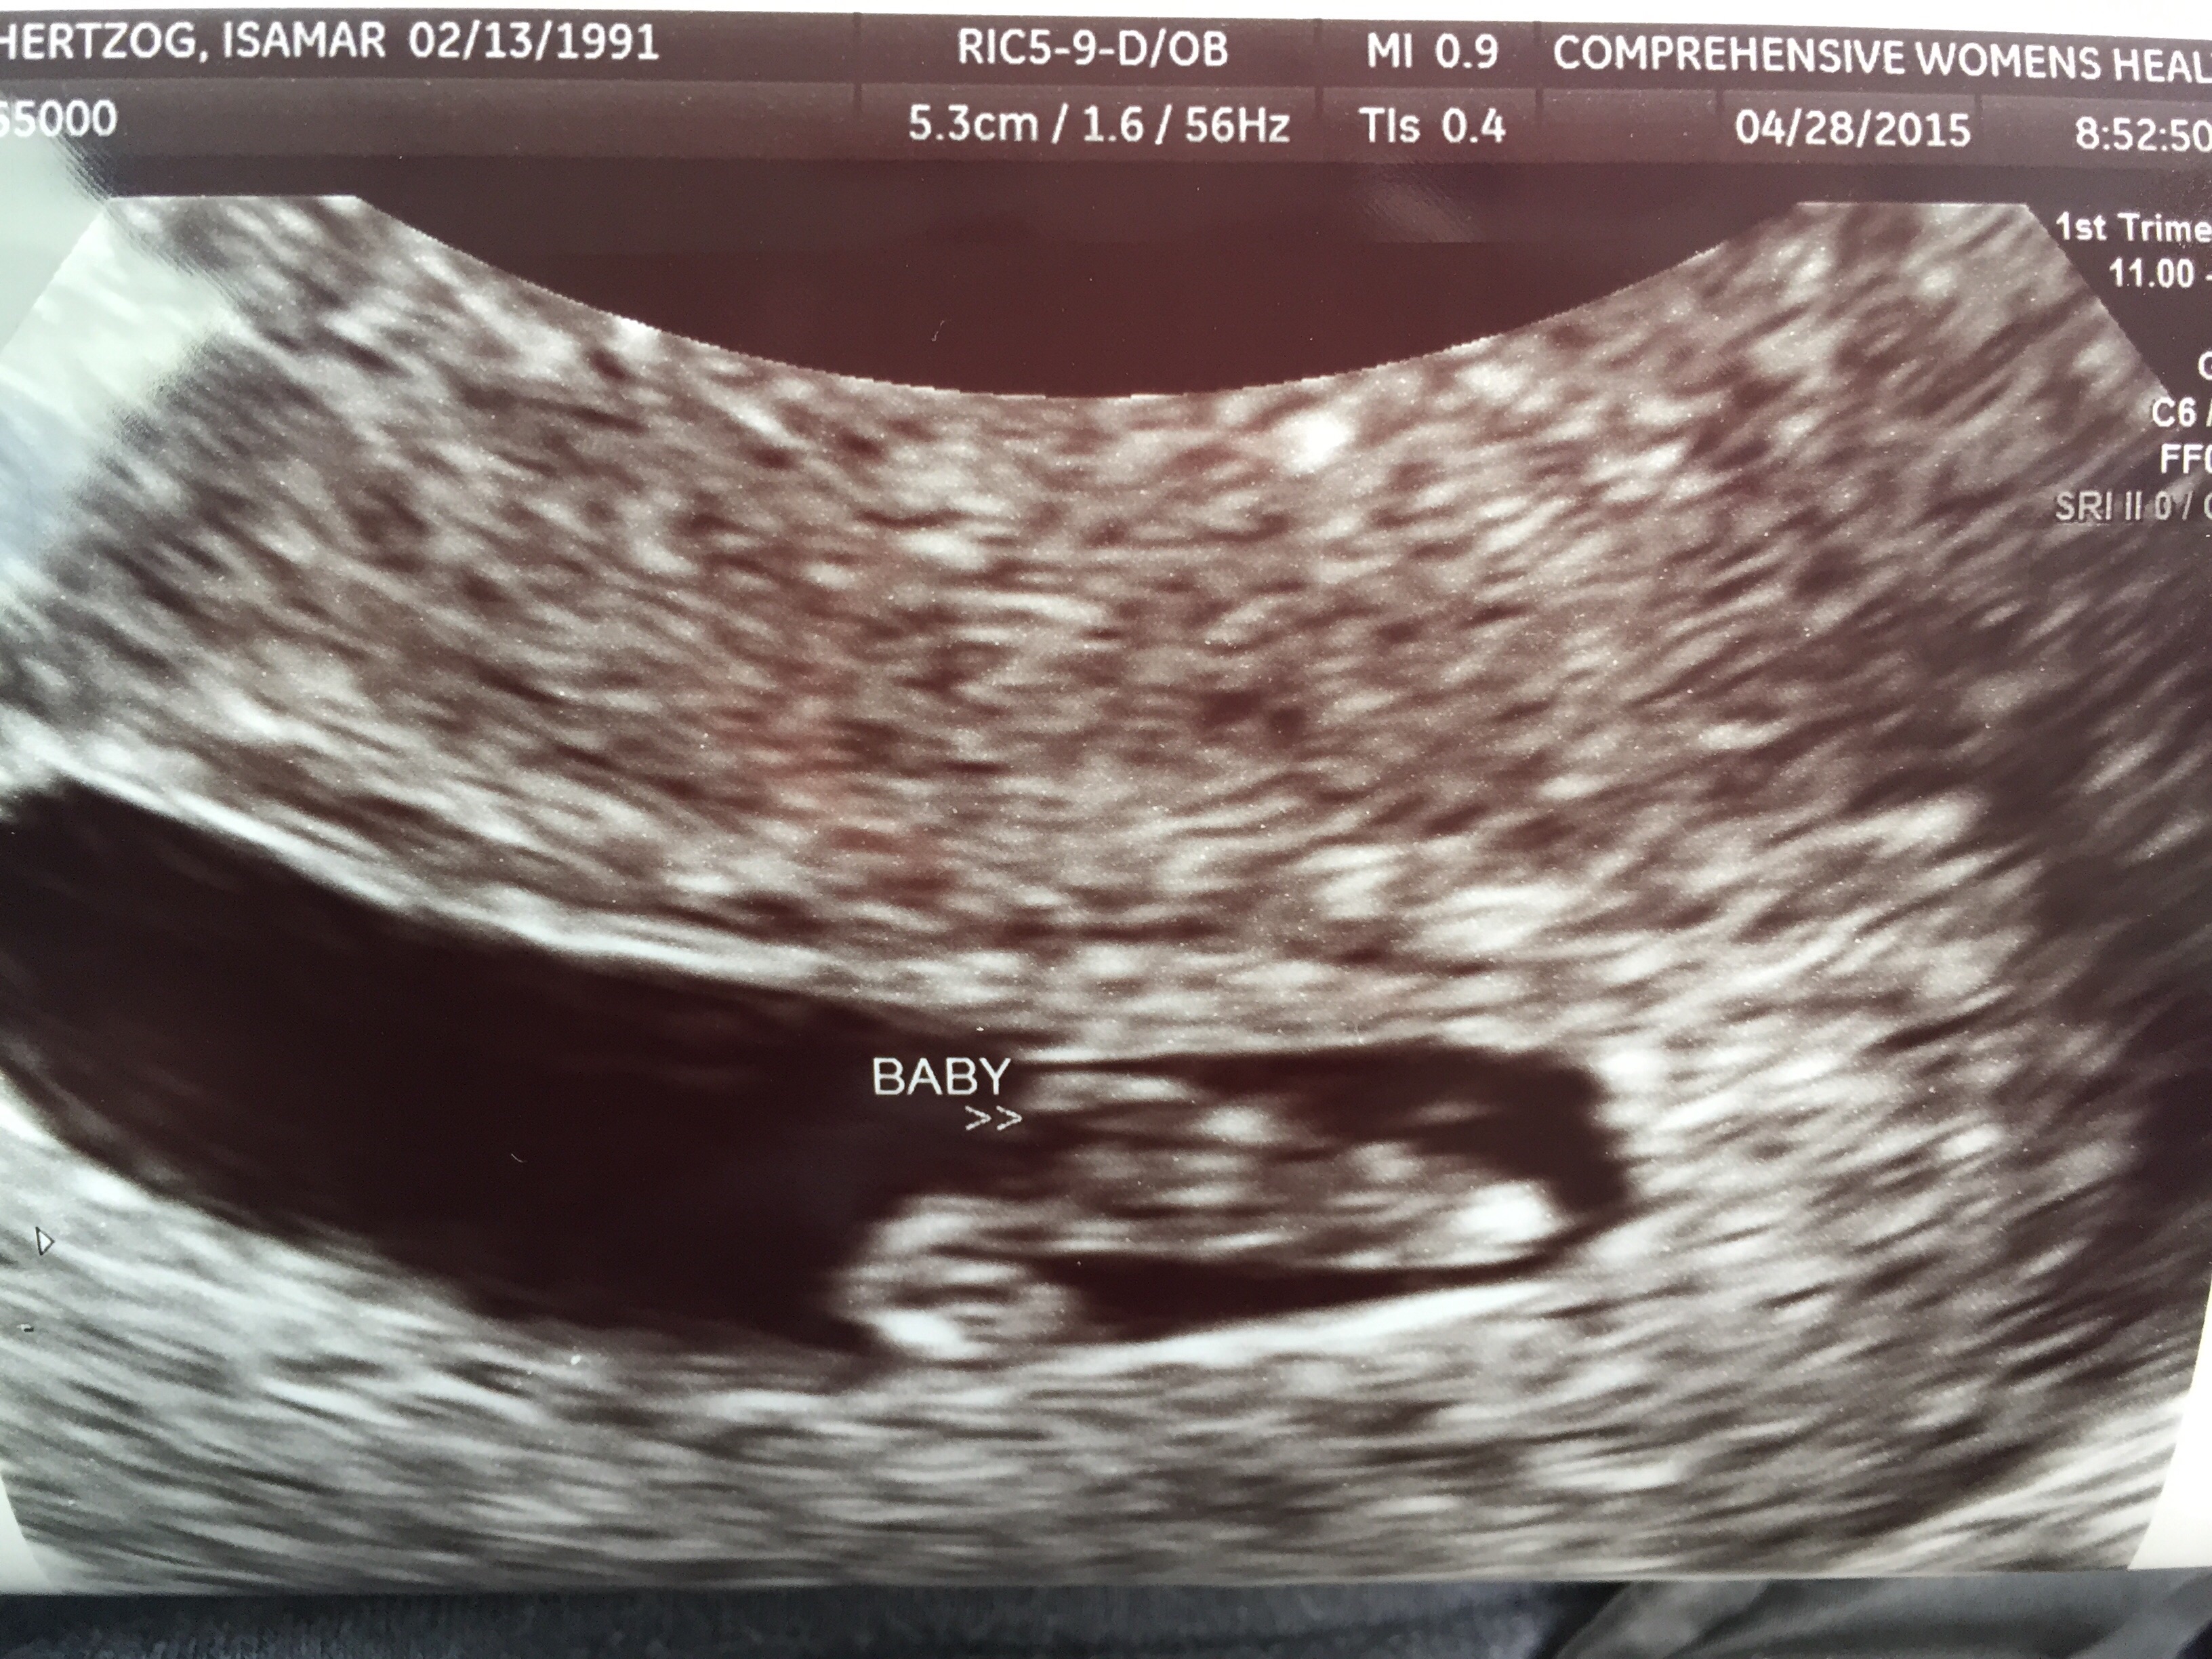

I don't have my pictures scanned in, but I guess I need too now! Wow I can't believe how baby like it looks at 9 weeks! That is insane. I got to see the heart beat, but my OB said we would listen next time!!! So excited!